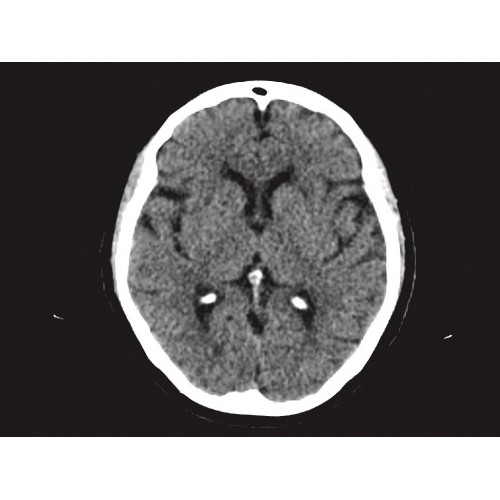

Позволяет проводить комплексные исследования всех анатомических зон, включая нейровизуализацию, ангиографию, исследования органов грудной и брюшной полости. Особенно эффективен для раннего выявления онкологических заболеваний.